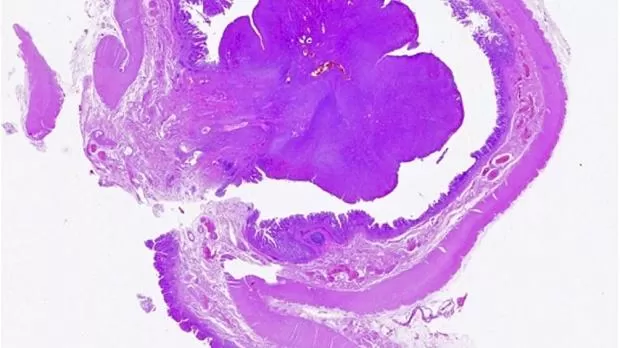

Микроскопическое исследование новообразования показало мезенхимальную пролиферацию, состоящую из веретенообразных клеток — мономорфных и без значительной атипии, организованных в пучки, ассоциированных с диффузной лимфоцитарной инфильтрацией, плазматическими клетками и эозинофилами, распространяющимися на слизистую оболочку и инфильтрирующими подслизистую оболочку (рис. 3, 4).

Рисунок 3 [1].

Рисунок 4 [1].

При иммуногистохимическом исследовании: положительно для SMA, отрицательно для цитокератина, десмин, S-100, Мелан-А, CD34, CD117, DOG-1, CD21, CD23, CD1a и ALK. На основании этих результатов диагноз IMT был подтвержден.